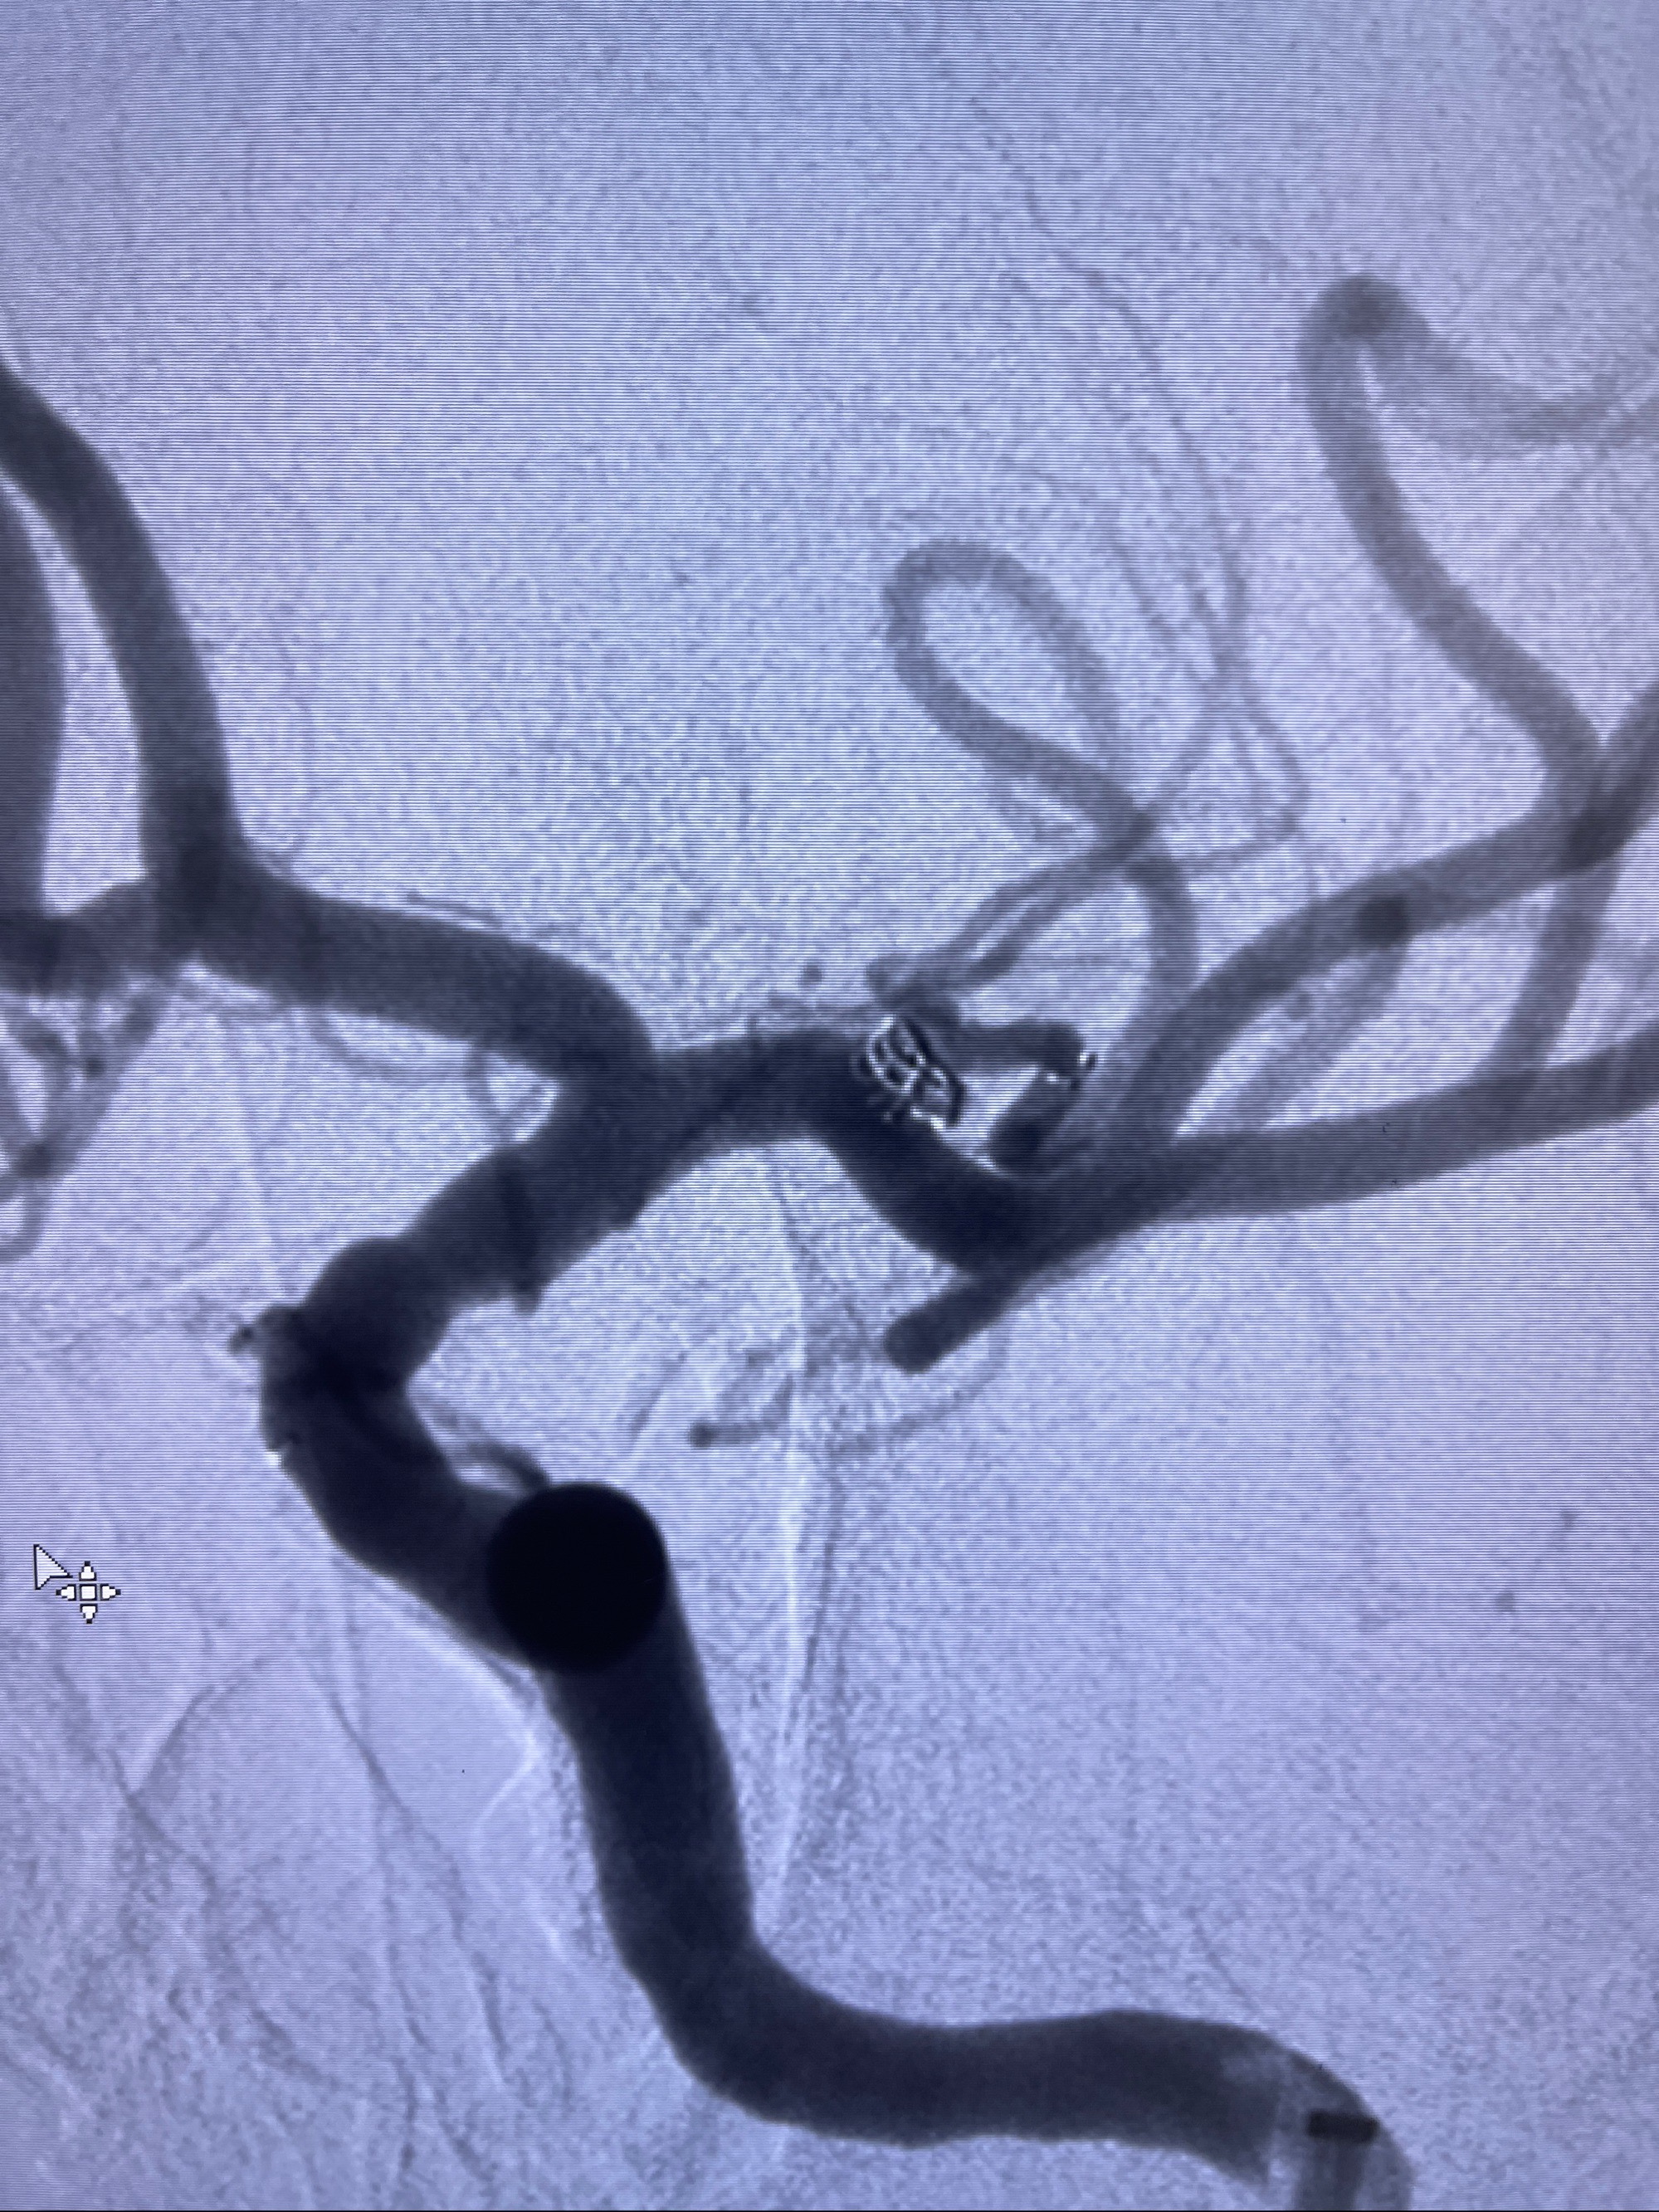

麻醉苏醒佳,遵嘱动作

术后即刻CT